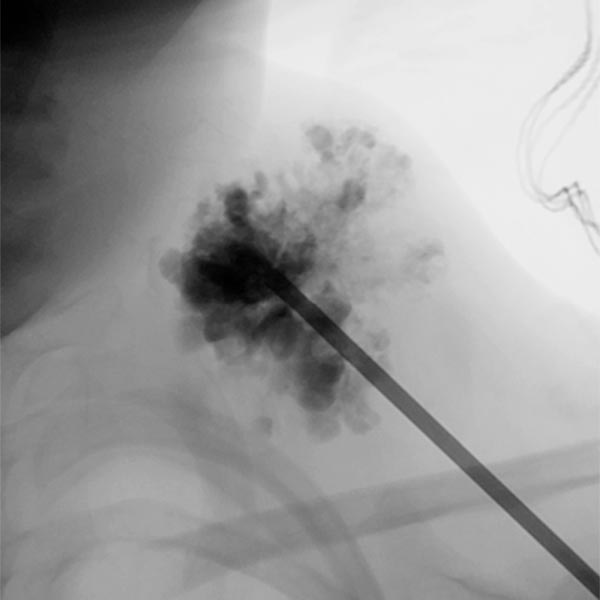

Digital subtraction angiography after contrast injection via the same needle also shows very clearly the almost complete filling of the venous malformation from this needle position. Only small, very thin-lumen communicating veins present themselves. Therefore, a large part of the venous malformation can be sclerosed from this needle position.

In the fluoroscopic control (lateral plane) after injection of 8 ml of polidocanol foam (3%, 1 : 4 foamed in air), the entire venous malformation is filled with the non-contrasting foam. The previously contained contrast medium is almost completely displaced by the sclerosing foam. Thus there is a good chance that the lesion will be very largely closed by the procedure.